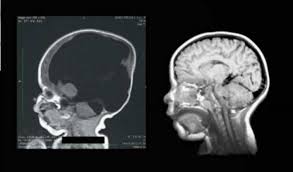

3歳時の脳スキャンで、脳は正常の約80%まで拡大。英国の全国放送が、その歩みを記録。